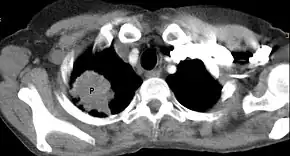

| Chest radiograph showing a Pancoast tumor (labeled as P, non-small cell lung carcinoma, right lung), from a 47-year-old female smoker. | |

Diagnosis of Pancoast tumor is usually made after evaluating clinical symptoms and imaging. Chest X-ray is a good screening test even though Chest CT scan can provide a better resolution and extent to which internal organs are being compressed.